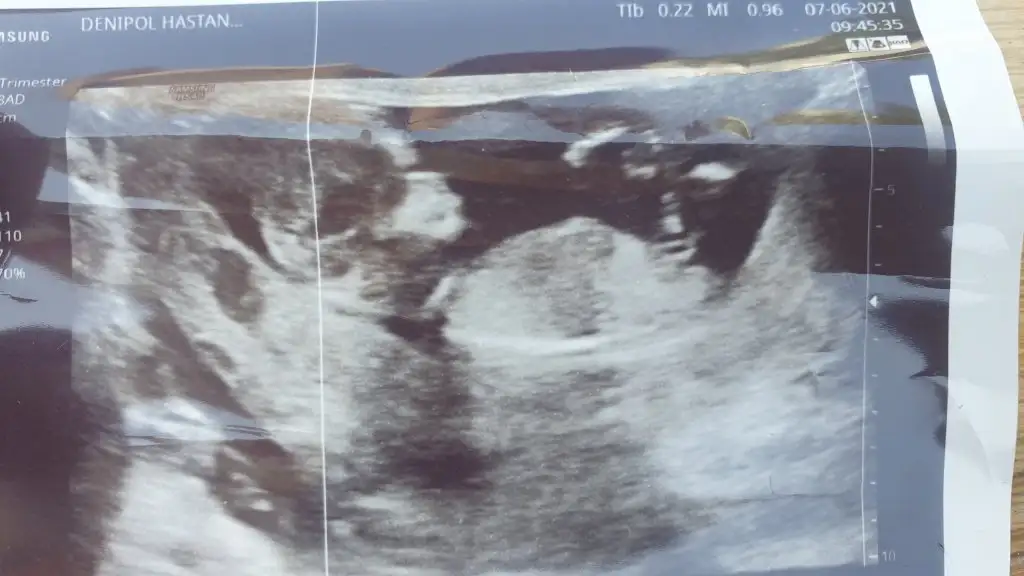

Selamlarr burdan da sorayım dedim Ikra meyra tahminiz nedir bizim içinde

Eklentiler

• 85C70FF4-763B-45AC-B39C-8BE5E7944E3E.webp

24,1 KB · Görüntüleme: 79